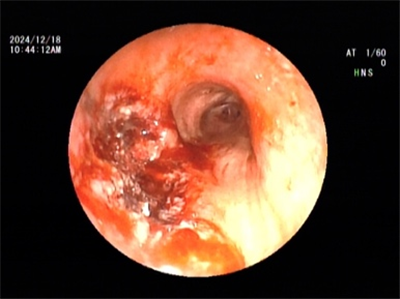

2024年12月18日,在王海龙主任的带领下,医疗团队凭借精湛的医术和丰富的经验,在支气管镜的精准引导下,将消融针准确插入肿瘤部位,运用圈套、冻切等方式对肿瘤组织进行消融。然而,由于肿物堵塞左主支气管开口,在使用电圈套及冷冻技术切除肿物的过程中,发现阻塞范围广泛,若进行完全冻融操作,时间过长且手术风险过高,因此,医疗团队先予以部分消融,解除了肿物对气道的阻塞。2025年1月22日,医疗团队为患者行第二次气管镜下冻融治疗,成功完全解除气管阻塞。术后,患者呼吸明显顺畅,各项生命体征平稳,恢复情况良好。